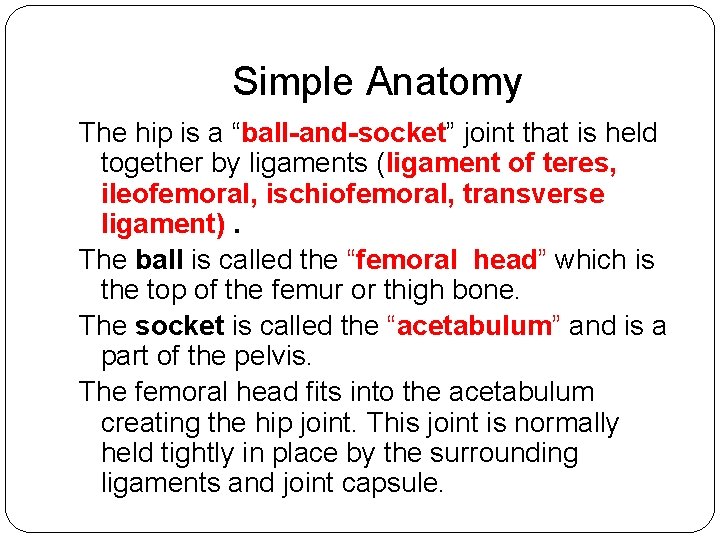

Simple Anatomy The hip is a “ball-and-socket” joint that is held together by ligaments (ligament of teres, ileofemoral, ischiofemoral, transverse ligament). The ball is called the “femoral head” which is the top of the femur or thigh bone. The socket is called the “acetabulum” and is a part of the pelvis. The femoral head fits into the acetabulum creating the hip joint. This joint is normally held tightly in place by the surrounding ligaments and joint capsule.